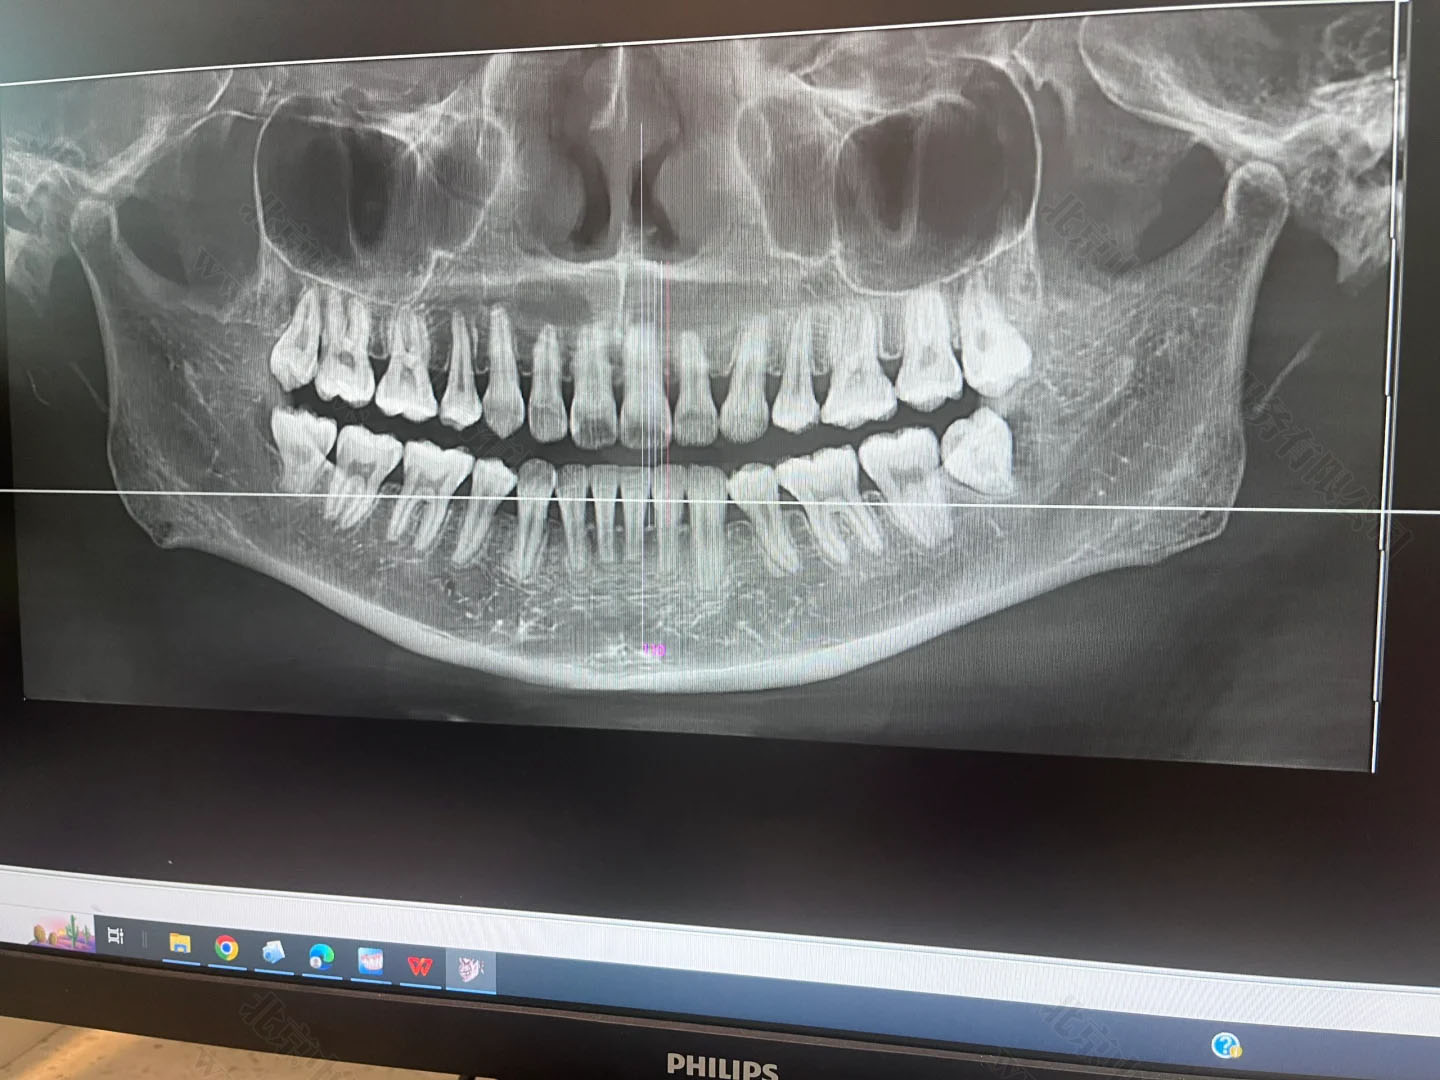

牙片也屬于放射診療

只要是裝了牙片機(jī),不管是常規(guī)拍片還是全景片,這類設(shè)備都屬于放射類診療儀器,必須先提交項(xiàng)目的放射防護(hù)預(yù)評(píng)價(jià)報(bào)告,也就是確認(rèn)這個(gè)設(shè)備對(duì)人有沒(méi)有輻射危害,能不能安裝和使用。

在施工前,這個(gè)報(bào)告必須提前交到北京市衛(wèi)生部門(mén)審核。審批通過(guò)了才能動(dòng)工裝修,否則一切都白忙活。牙片雖然是“輕放射”,但防護(hù)的流程跟CT、核磁一樣,不能跳過(guò)。

拍片前后還得驗(yàn)收

項(xiàng)目完工后也不是馬上就能拍牙片,還得請(qǐng)專業(yè)機(jī)構(gòu)做一個(gè)職業(yè)病危害控制效果評(píng)價(jià),就是看你這機(jī)器在使用過(guò)程中,周邊有沒(méi)有多余輻射,會(huì)不會(huì)對(duì)醫(yī)生、患者和旁人造成傷害。做完后,還得向衛(wèi)生部門(mén)提交設(shè)備驗(yàn)收申請(qǐng),包括檢測(cè)報(bào)告、施工資料等一整套材料。

只有經(jīng)過(guò)這道驗(yàn)收關(guān),診所才可以拿到《放射診療許可證》,正式開(kāi)展拍片業(yè)務(wù)。這個(gè)流程平均要花上兩三個(gè)月,不提前準(zhǔn)備就容易耽誤診所開(kāi)張。